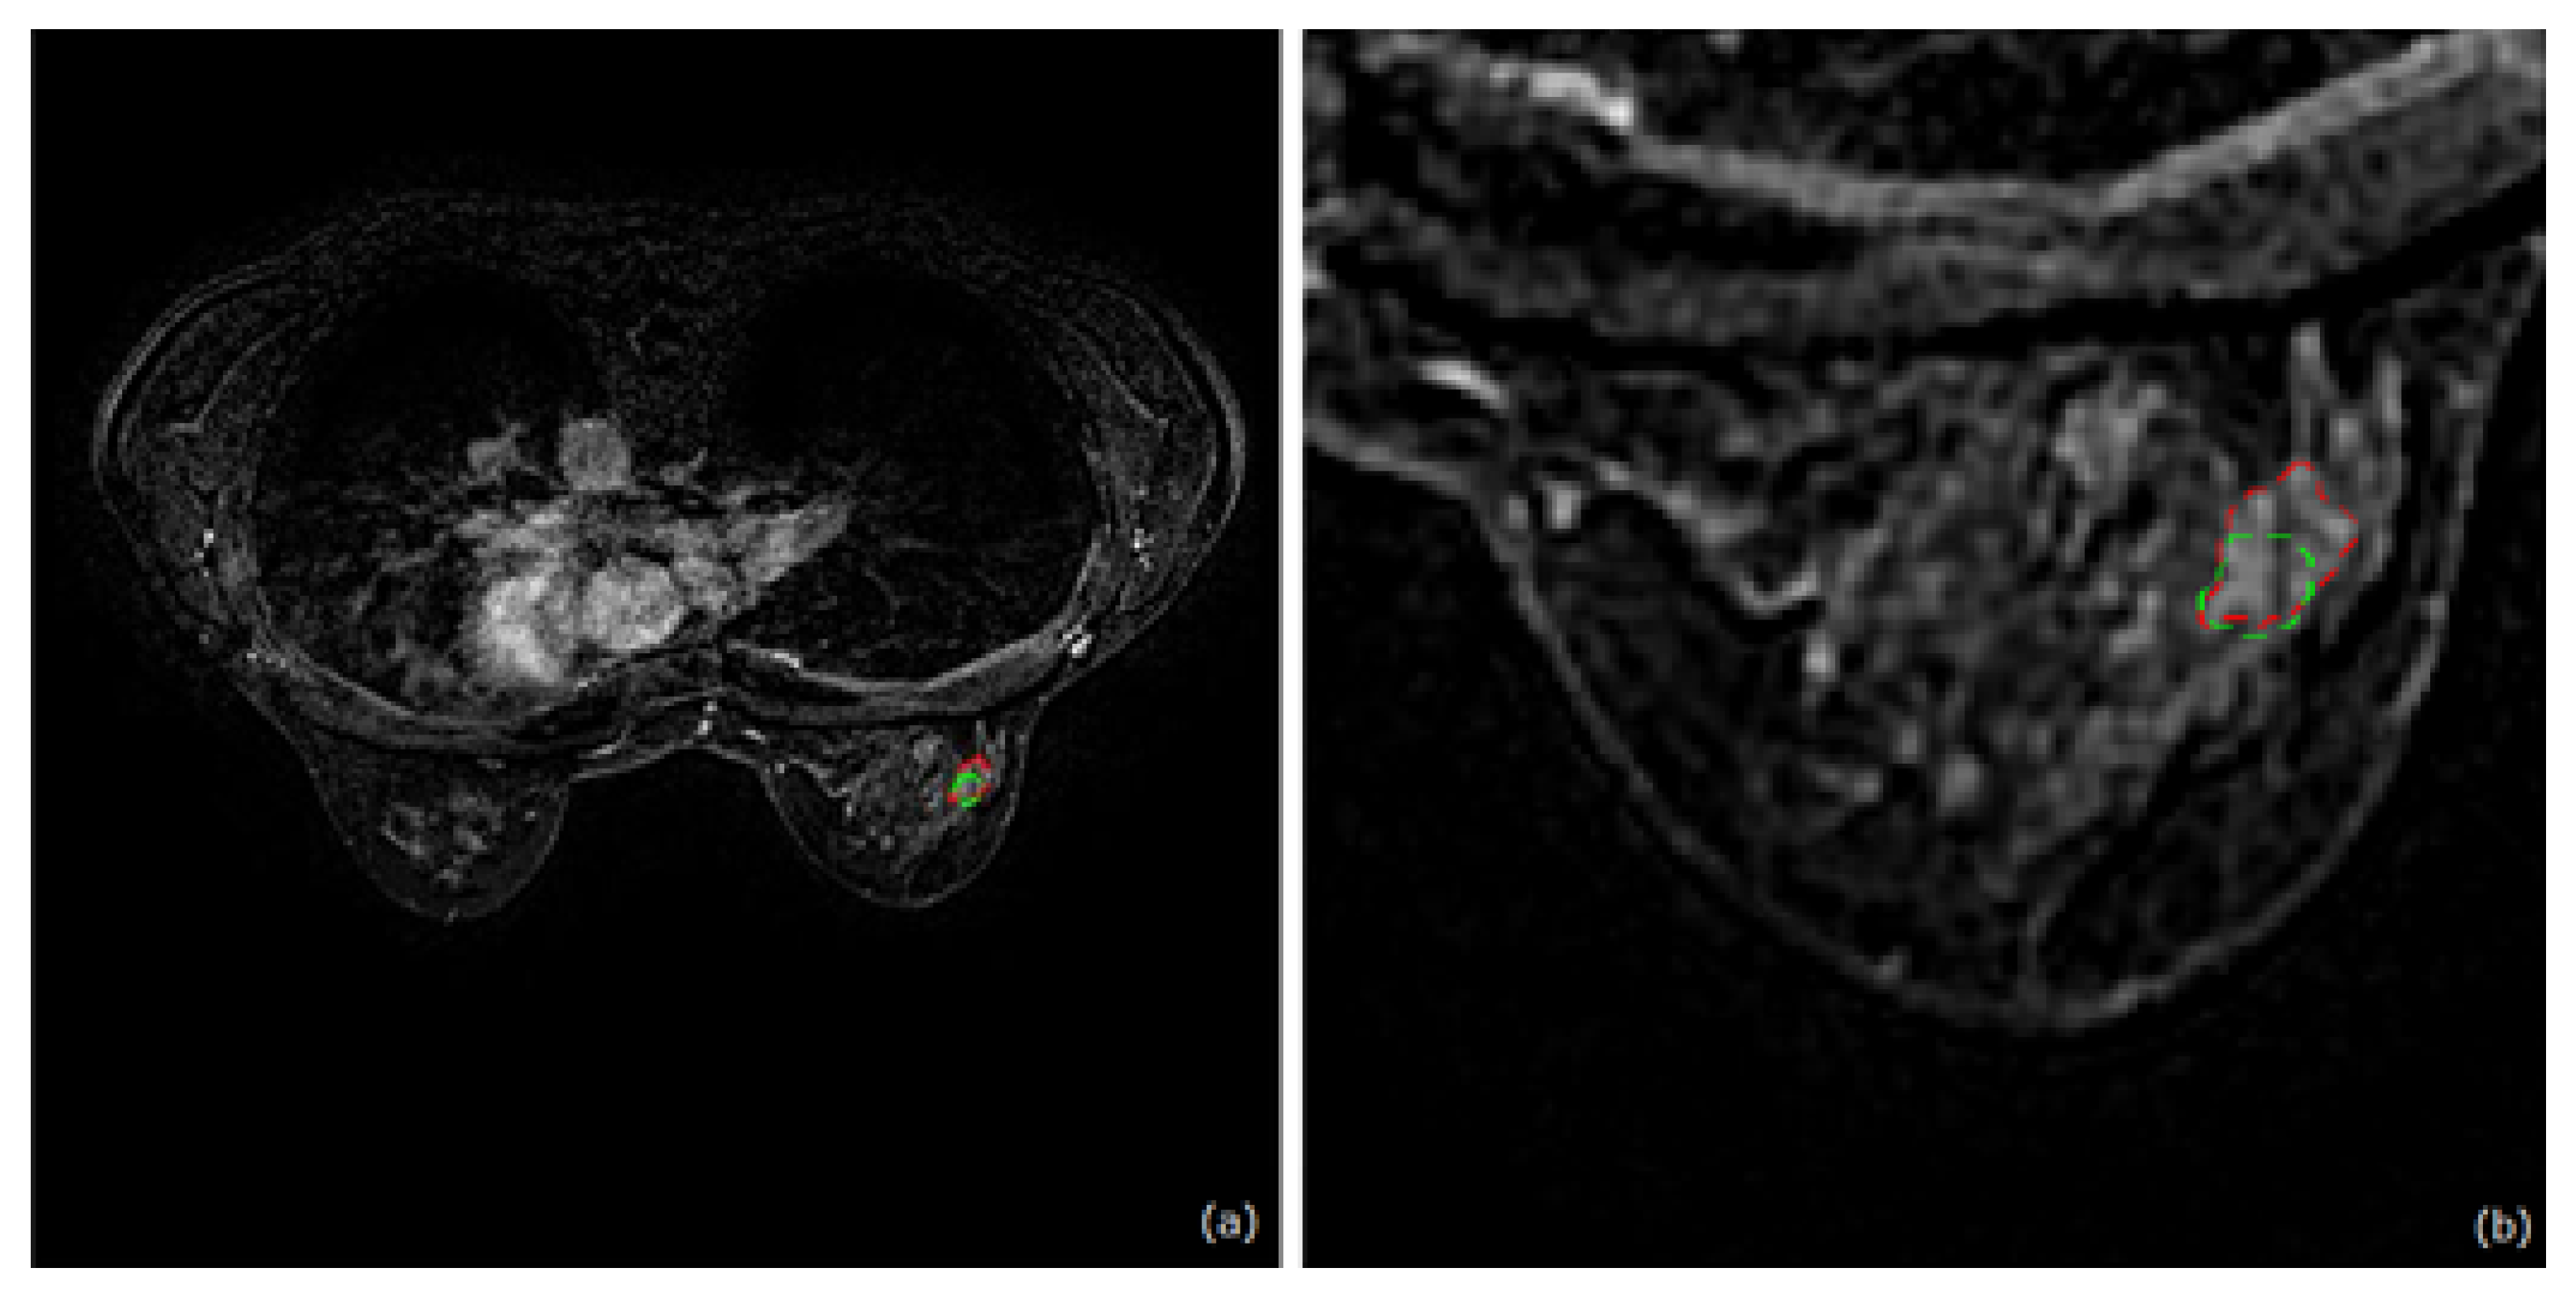

3.2.1. Dataset Loading and ROI Selection

5.4.1. Case with Low Contrast-Enhanced Mass